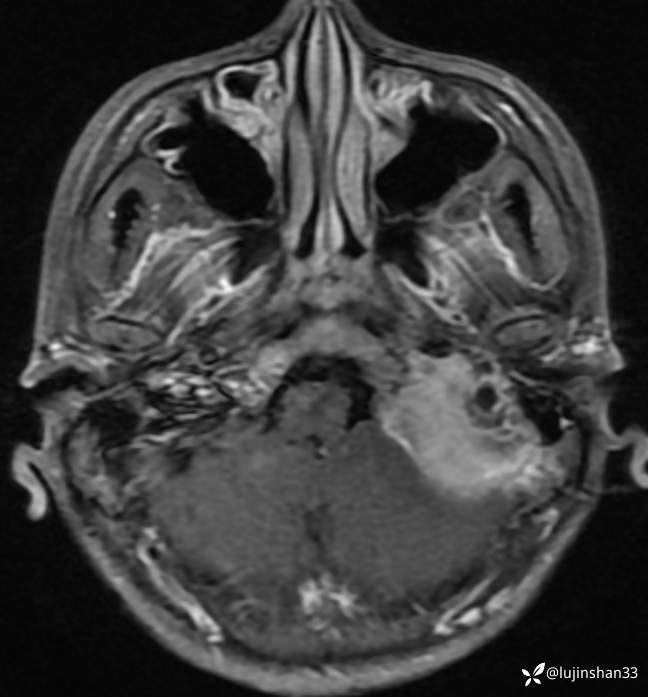

术后1年半复查CT及MRI

二次手术后1年半,肿瘤切除术后,未见复发

【现病史及既往史】:患者2年前无明显诱因出现左耳搏动性耳鸣、听力下降,耳鸣持续存在,伴轻度头晕,无眩晕及恶心、呕吐,无左侧外耳道流脓、流血,无视力下降,于2018-09-19在XXX市第一人民医院行颞骨CT及颅脑核磁示:左侧岩骨-桥小脑角区占位性病变,伴骨质破坏,考虑肿瘤性病变,于2019-02-19日于在我科住院行“经枕颈联合径路颞骨、颈静脉球窝及后颅窝肿瘤切除+腹部脂肪取出术腔填充+外耳道封闭”,病理结果(2019-2-19,我院)(左颞骨、左颞骨后颅窝、后颅窝硬脑膜) 富于破骨样巨细胞的肿瘤,背景为基质细胞梭形,界限不清,部分区域可见出血,局部见反应性骨形成,考虑为骨巨细胞瘤。送检瘤组织大小分别为1.2x1.2x0.7cm、7x6x2.5cm、3x2x0.8cm。(左颈部)淋巴结未见转移肿瘤(0/2)。免疫组化结果:p63(部分+),SATB2(+),Ki-67(+10%)。术后定期门诊随访,于2019-09-02行颞骨CT示:左侧颞骨骨巨细胞肿瘤术后改变,左后颅窝异常强化灶累及左侧颞骨斜坡,考虑复发,为进一步手术治疗来我院,以"颞骨骨巨细胞瘤术后(左)"收住入院。